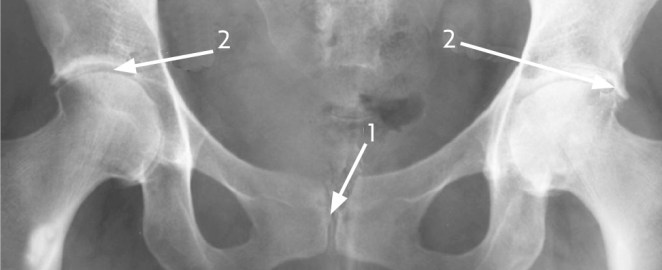

La condrocalcinosis o imágen radiológica producida por el depósito de pirofosfato se aprecia característicamente en el ligamento triangular del carpo, la rodilla y la sínfisis del pubis.

Proyección Anteroposterior de la pelvis: 1) depósito de pirofosfato cálcico en la sínfisis del pubis 2) Depósitos en la articulación coxofemoral con esclerosis subcondral y presencia de osteofitos.